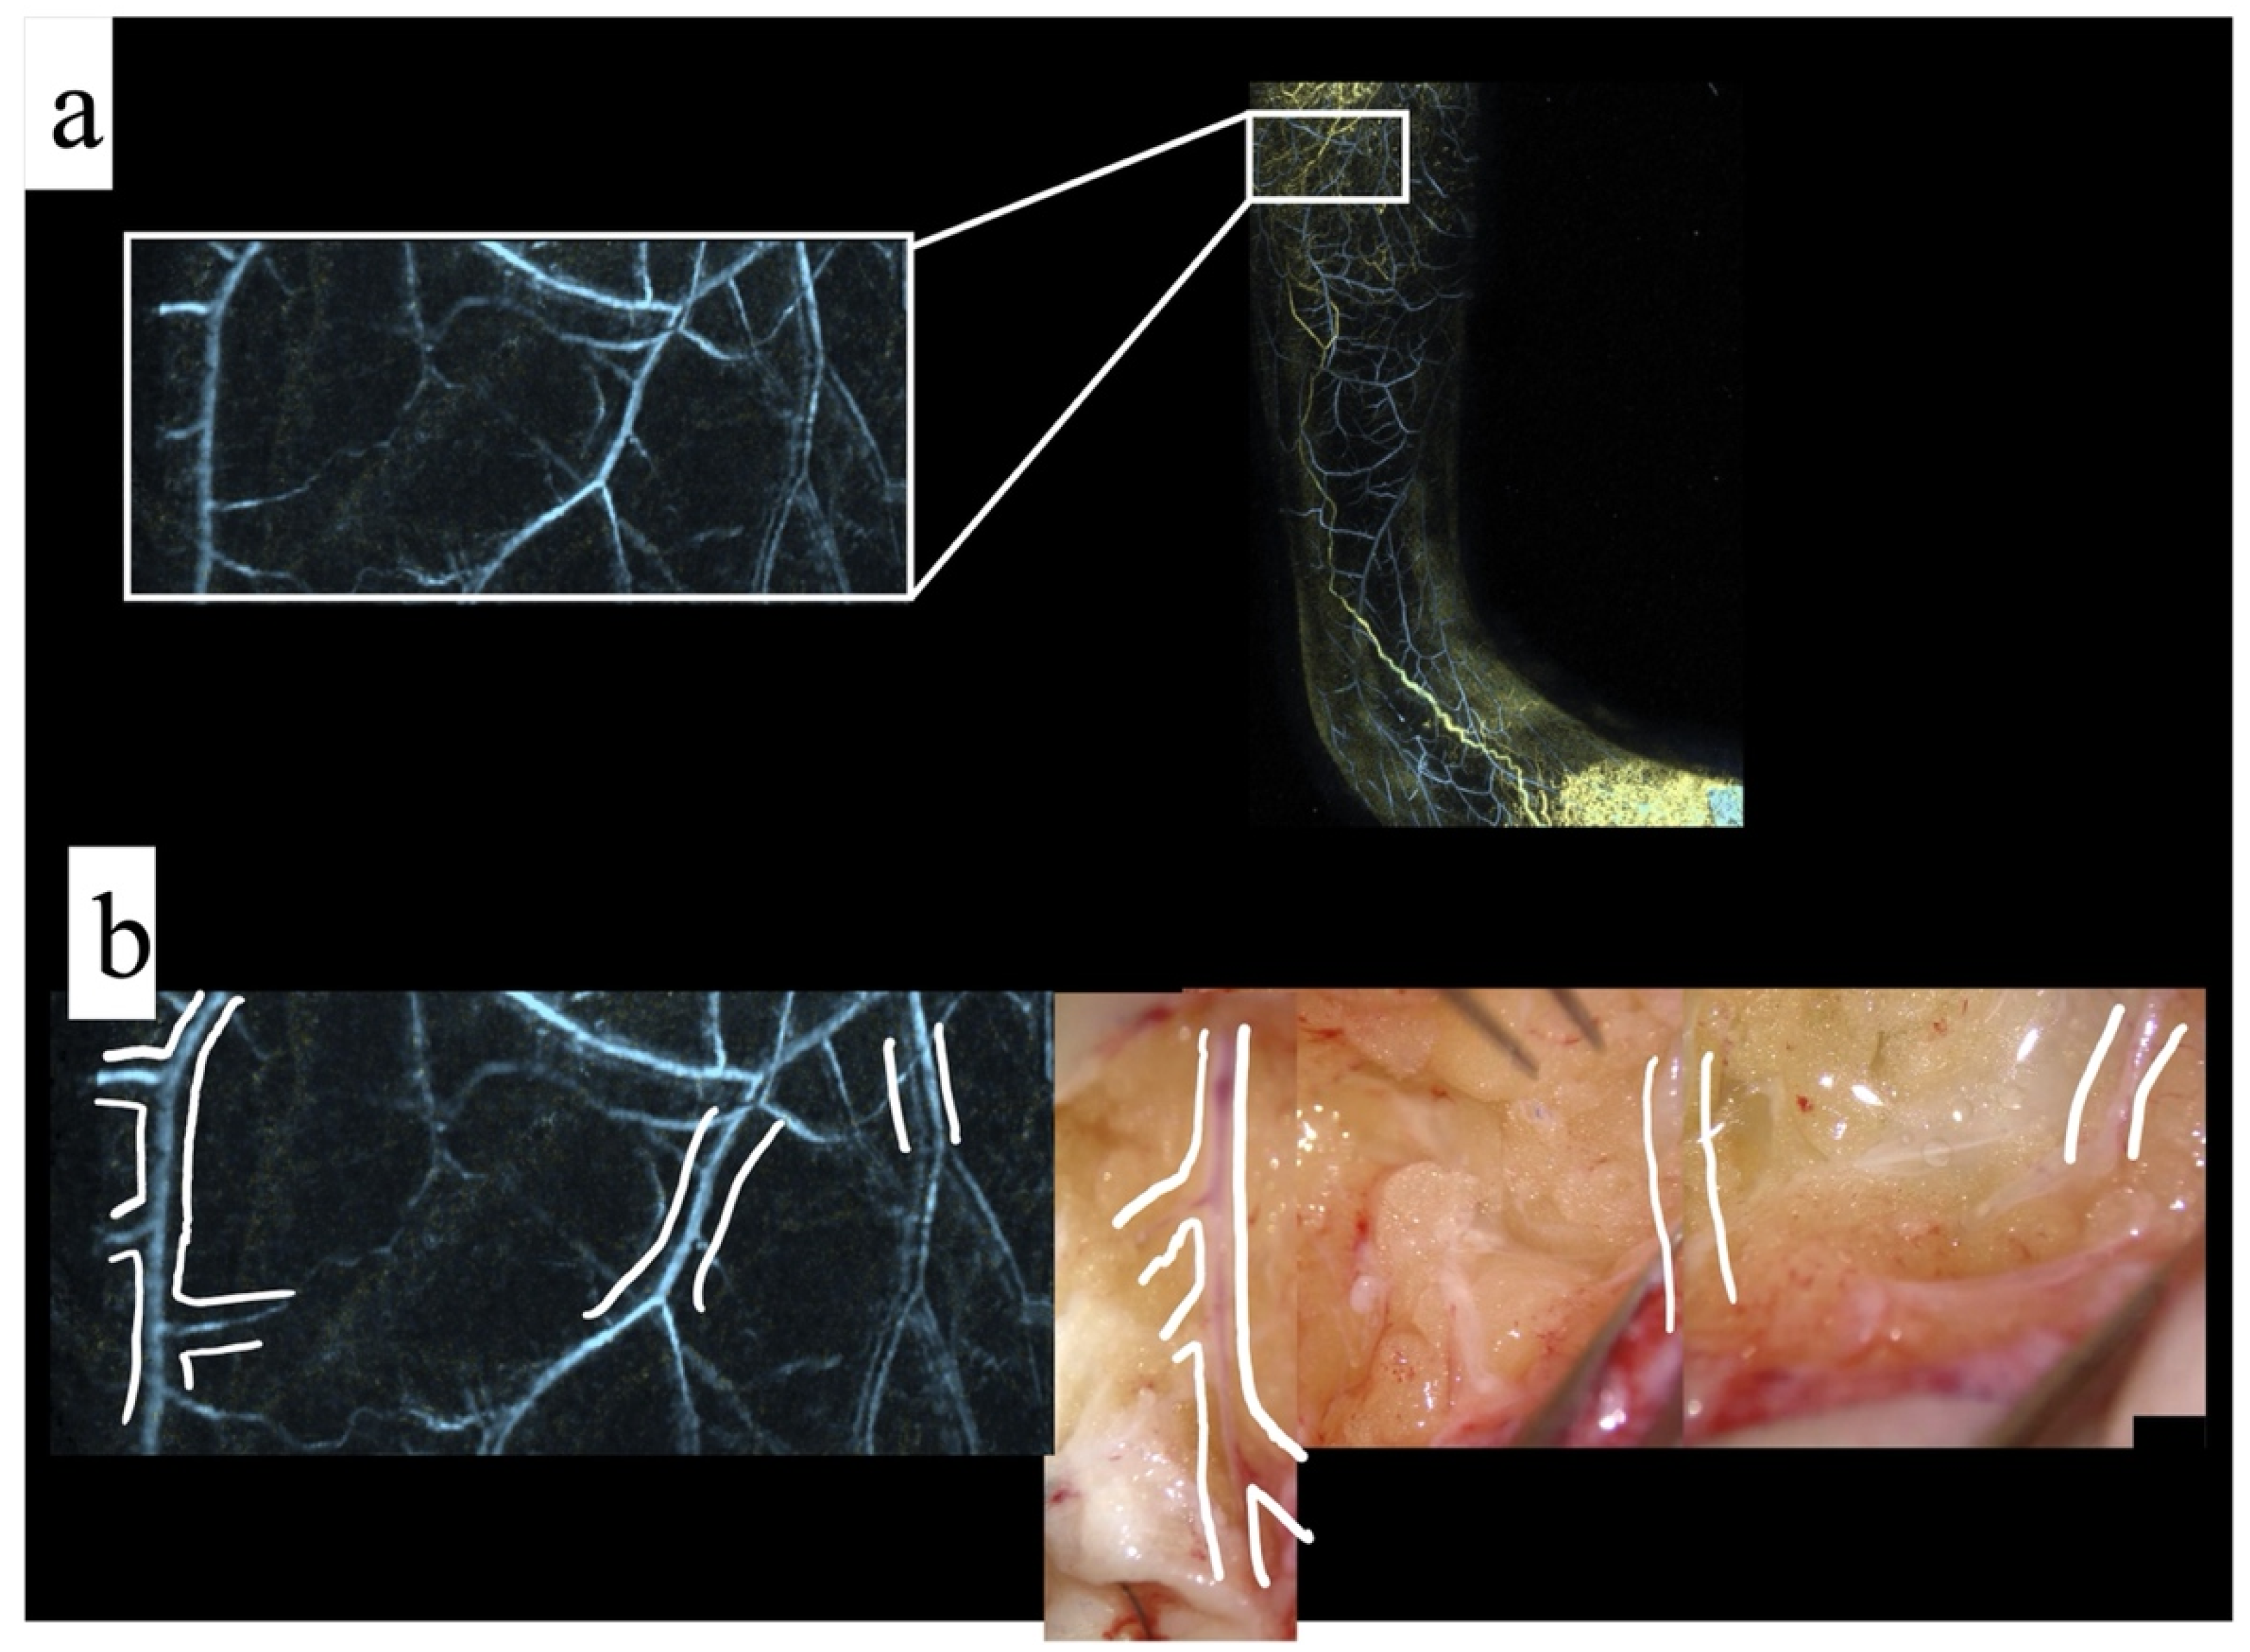

3.1. Result: Photoacoustic Imaging Match with Surgical Findings

3.2. Result: Transfer the Photoacoustic Image to the Actual Surgical Field